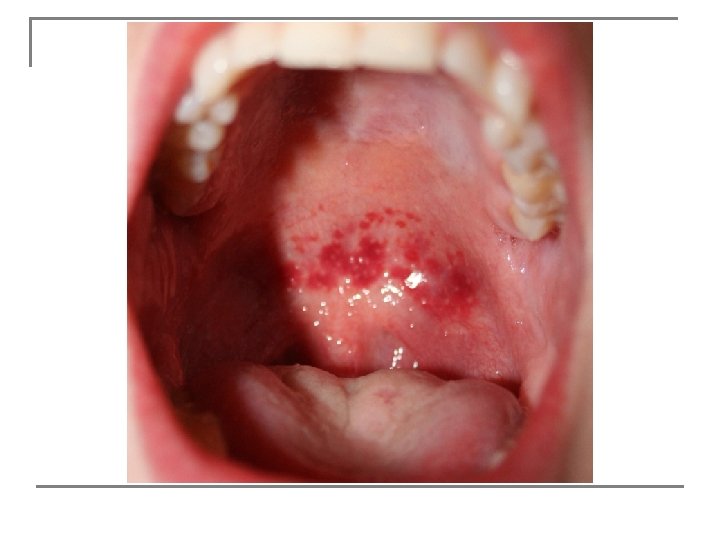

n Bacteria, viruses, protozoans, fungi, and other parasites called pathogens are capable of causing a change that disrupts the homeostasis in the body.

n Any disease caused by the presence of pathogens in the body is called an infectious disease. The main sources of pathogens are soil, contaminated water, and infected animals, including other people